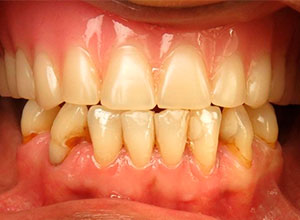

Antes de la Cirugía de Implantes